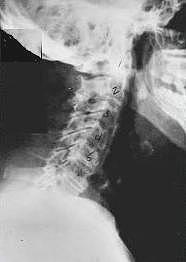

Subluxation Degeneration

Subluxation Degeneration This is a representation of one type of subluxation. A subluxation, as defined by the Association of Chiropractic Colleges is: "A subluxation is a complex of functional and/or structural and/or pathological articular changes that compromise neural integrity and may influence organ system function and general health." When a subluxation occurs it causes nerve interference in some portion of the body affected by those nerves. The subluxation causes changes to the structure as well as the nerves. These changes get progressively worse as time is allowed to work on the subluxated area of the spine. These changes take the form of ongoing degeneration known as "subluxation degeneration". By understanding the type and amount of changes, it is possible to reasonably estimate the time subluxations have been present in a spine. Having this information is useful in understanding the time and effort needed for correction.

Phase One - Subluxation Degeneration

Subluxation Degeneration - Phase One Phase One Subluxation Degeneration is seen in subluxations that have been present for up to twenty years. This phase is characterized with a loss or change in the normal curve in the spine. On this example you can see that the normal forward (lordotic) curve is lost. This spine even has developed a reverse curve in the neck. The disc spaces have also begun to exhibit a slight change in shape. One good point is that the bodies of each of the vertebrae (the square part in front) still exhibits clean clear borders. Segmental motion may be abnormal but overall motion is probably not affected. Chiropractic reconstructive care for a phase one can take from 6 to 18 months. More than 80% of people with Phase One Subluxation Degeneration have no pain. Therefore, if left uncorrected, phase one continues to progress with time until it eventually reaches the next phase.